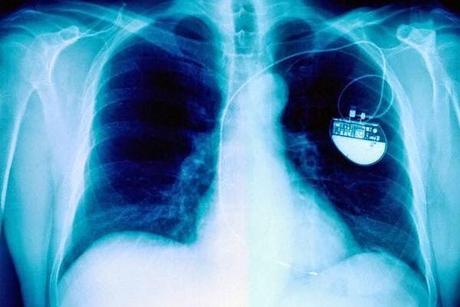

Establecer la paternidad de las grandes invenciones puede ser una tarea complicada y no exenta de polémica.Tal vez por eso, aunque en su Colombia natal Jorge Reynolds es reconocido como el inventor del marcapasos, su nombre no siempre figura en los artículos que dan cuenta de la historia de este aparato.Reynolds, sin embargo, parece más interesado en el futuro que en el pasado del invento.Este ingeniero en electrónica bogotano, de 75 años de edad, acaba de presentar un prototipo capaz de revolucionar el dispositivo del que dependen millones de personas con problemas cardíacos de todo el mundo.Se trata de un "nanomarcapasos" que mide la cuarta parte de un grano de arroz y no utiliza baterías, sino una combinación de energía piezoeléctrica (que se produce al comprimir cierto tipo de cristales) y la energía producida por el propio corazón.Para esto último emplea un "puente aurículo-ventricular", inspirado por las investigaciones de Reynolds sobre el corazón de las ballenas.Aprendiendo de la naturaleza

El nanomarcapasos es un ejemplo de lo mucho que ha avanzado la tecnología desde que Reynolds construyó su primer marcapasos, en 1958, para salvarle la vida a un paciente de la clínica Shaio de Bogotá."Fue una cuestión que al paciente, un sacerdote, no había nada que ofrecerle, y el jefe de cirugía me convenció que pusiéramos el marcapasos", le dijo a BBC Mundo."El sacerdote estuvo totalmente de acuerdo, porque sabía que si no se hacía eso se iba a morir. Se cruzaron los dedos y resulta que funcionó", recuerda Reynolds, quien en esa época se acabada de graduar en la Universidad de Cambridge y descubierto "que la electrónica funcionaba divinamente en la medicina y particularmente el corazón, que es un sistema totalmente eléctrico".Ese marcapasos, que se conserva en la Academia nacional de Medicina de Colombia, era más grande que una batería de auto y según Reynolds se trató del primero con electrodos internos del mundo y "el primero que le colocó a un paciente de forma definitiva"."Muy cercano a esto están los suecos, que hicieron su primer marcapasos en el Instituto Karolinska. Pero ese primer marcapaso de los suecos le duró al paciente tres horas, el mío le duró al paciente 18 años", dijo.Según Reynolds, entre los dos inventos hubo una diferencia de unos quince días.Aunque mientras el suyo era un marcapasos externo, el desarrollado por Rune Elmqvist, en Suecia, era un marcapasos implantable."Esa era su ventaja. Tenía unos sistemas de baterías y demás muy primitivos. Pero la idea, absolutamente genial, de pensar en una cosa mucho más avanzada", reconoció el investigador colombiano.La disputa por el título de padre del marcapasos, sin embargo, no se limita a Reynolds y Elmqvist.Australia reclama la paternidad del invento para Mark Lidwell, los estadounidenses para Albert Hyman y los canadienses para John Hopps (ver recuadro).Reynold, por su parte, destaca el trabajo del estadounidense Paul Zoll, a inicio de los años 50."El doctor Zoll fue una de las primeras personas que desarrollaron un marcapasos externo con electrodos externos", le dijo a BBC Mundo."Fue una de las primeras personas que estimuló el corazón, pero se necesitaban voltajes muy altos y entonces había una contracción de los músculos pectorales y después de una hora el dolor de eso no lo resistía el paciente", recuerda.Su modelo solucionó este problema empleando electrodos internos.Y aunque algo incómodo, por su peso y tamaño, el suyo también fue uno de los primeros marcapasos portátiles, otro paso importante en la evolución del invento.Hacia adelante